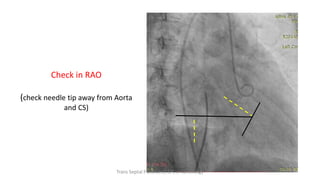

In the RAO

projection it is vital to keep

the tip of the needle

posterior to the pigtail or

running parallel

to the coronary sinus

catheter to avoid

puncturing the aortic root

Check in RAO

(check needle tip away from Aorta

and CS)